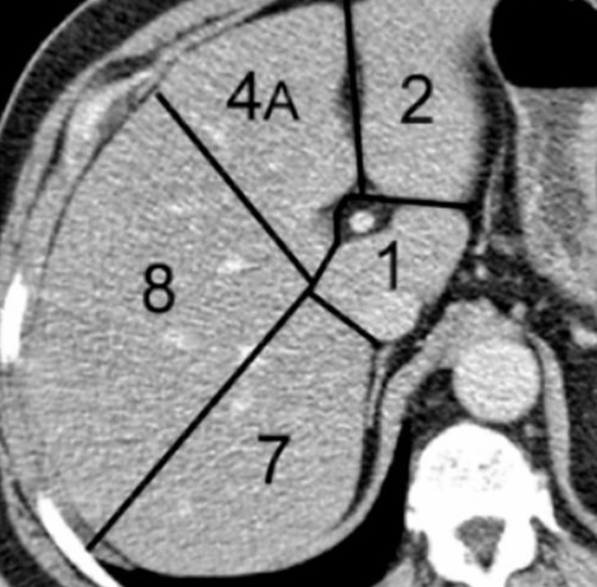

Plano divide o fígado em fígado direito e esquerdo funcionais (segmentação de Couinaud)?

A linha de Cantlie vai da fossa da vesícula biliar à veia cava inferior, seguindo a veia hepática média.

É utilizado como principal referência para a segmentação de Couinaud?

Veia porta.

A veia porta divide o fígado em segmentos supraportal e infraportal.

As veias hepáticas definem os planos verticais.

Segmentos hepáticos existem segundo Couinaud?

Oito segmentos (I a VIII).

Cada segmento é funcionalmente independente, com:

Ramo portal

Artéria hepática

Ducto biliar próprios